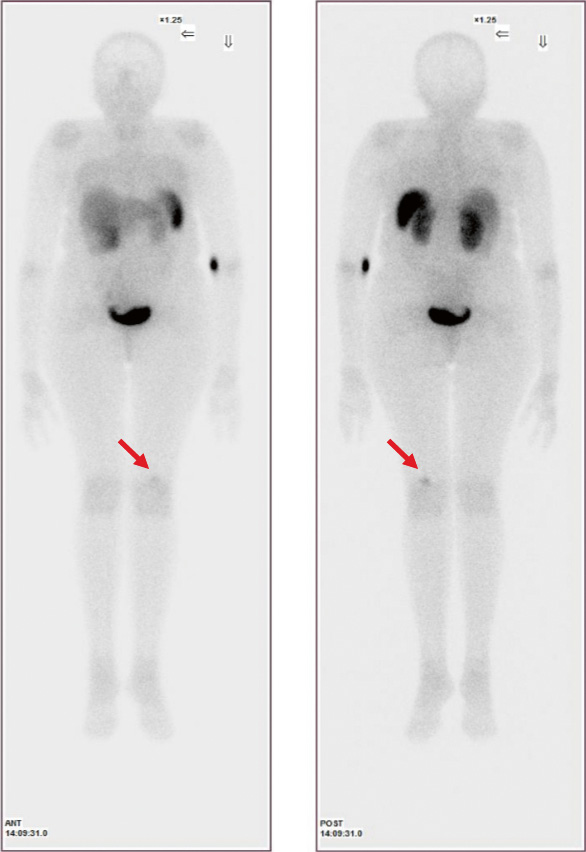

1. Fig. 1. Planar scintigraphy with 99mTc-Tectrotide patient G. | |